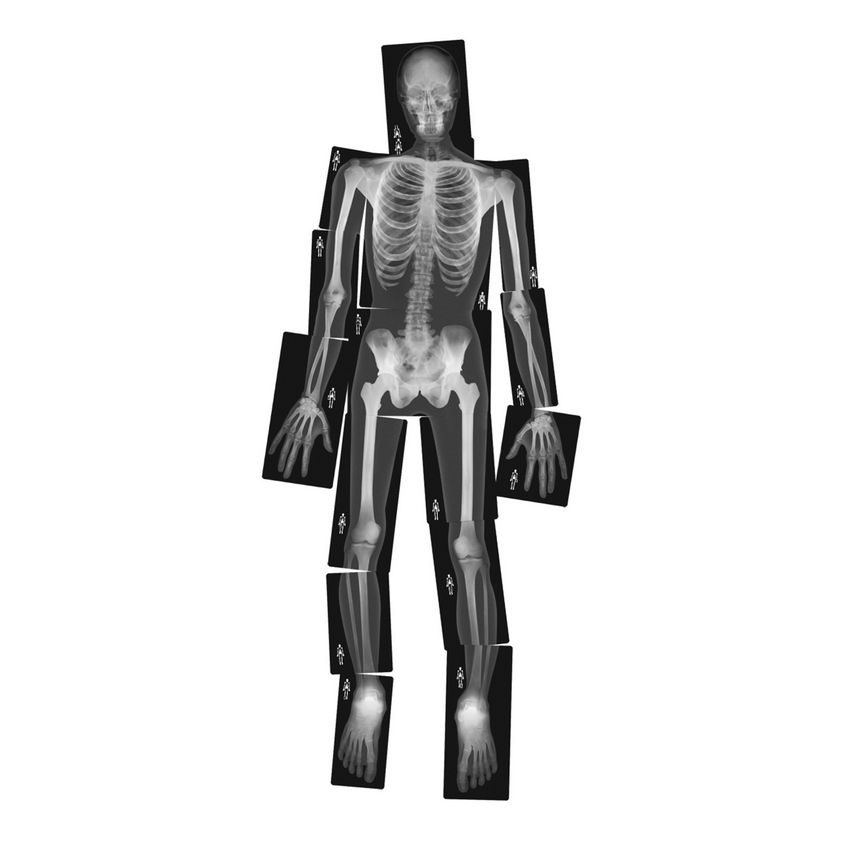

Hold these life-size human x-rays up to the light or use them on a light table and see every authentic detail of a real skeleton. Arrange the 18 pieces together to reproduce the entire body of a young adult 5' (1.5 m) tall. The teacher guide includes reproducible artwork and information on radiography. 18 pieces. Age 5+.